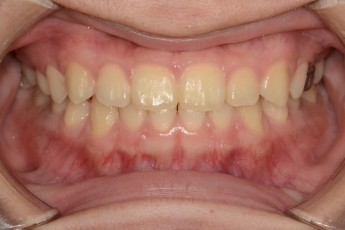

Before

After